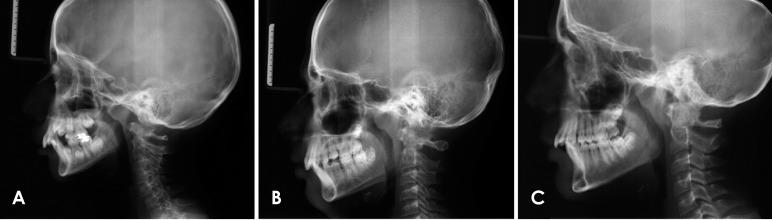

Totally 124 lateral cephalograms (47 for skeletal class I; 45 for skeletal class II, division 1; and 32 for skeletal class II, division 2) in pre-peak, peak, and post-peak growth periods were selected from the department archives. Thirteen landmarks, 4 angular and 4 linear measurements, and 4 proportional calculations were obtained. The ANOVA and Duncan test were applied to compare the differences among the study groups during the growth periods.

从科室档案中选取124张生长高峰前期、高峰期和高峰后期的头颅侧位片(骨骼I类47张;骨骼II类1分类45张;骨骼II类2分类32张)。获取了13个标志点、4个角度测量值、4个线性测量值和4个比例计算值。应用方差分析和邓肯检验比较各研究组在生长期间的差异。